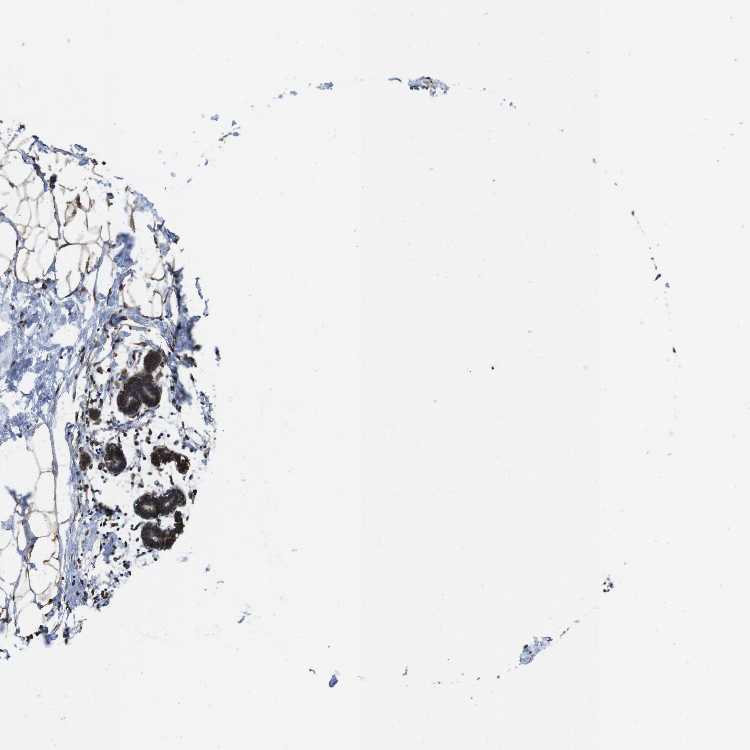

BREAST - Antibody stainingi

Antibody staining in the annotated cell types in the current human tissue is reported as not detected, low, medium, or high, based on conventional immunohistochemistry profiling in selected tissues. This score is based on the combination of the staining intensity and fraction of stained cells.

Each image is clickable and will lead to virtual microscopy that enables deeper exploration of all samples and also displays staining intensity scores, fraction scores and subcellular localization as well as patient and tissue information for each sample.

Antibody HPA012863

Adipocytes High

Glandular cells High

Myoepithelial cells High